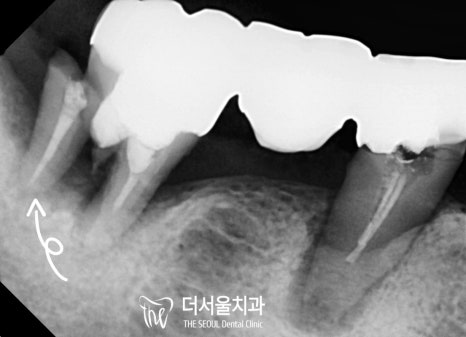

다행히 어려운 과정이었지만

별다른 문제 없이 마무리가 되었네요.

이쪽도 별반 다르지 않았기에

똑같이 뼈이식 임플란트 로 개선을 도왔습니다.

최종 보철을 올려드린 모습을 보면

텅텅 비어있던 곳이 새하얗고 예쁜 크라운으로

오밀조밀 잘 채워져 있습니다^^